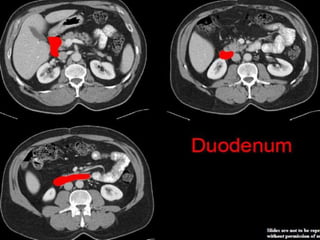

CT cross sectional anatomy.

CT – computedtomography. •Cross-sectional modality with capabilities for multiplanar reconstruction and dynamic imaging to assess vascularity •Tube rotates around the body and a circle of stationary detectors detects the penetrating x-rays forming an image.